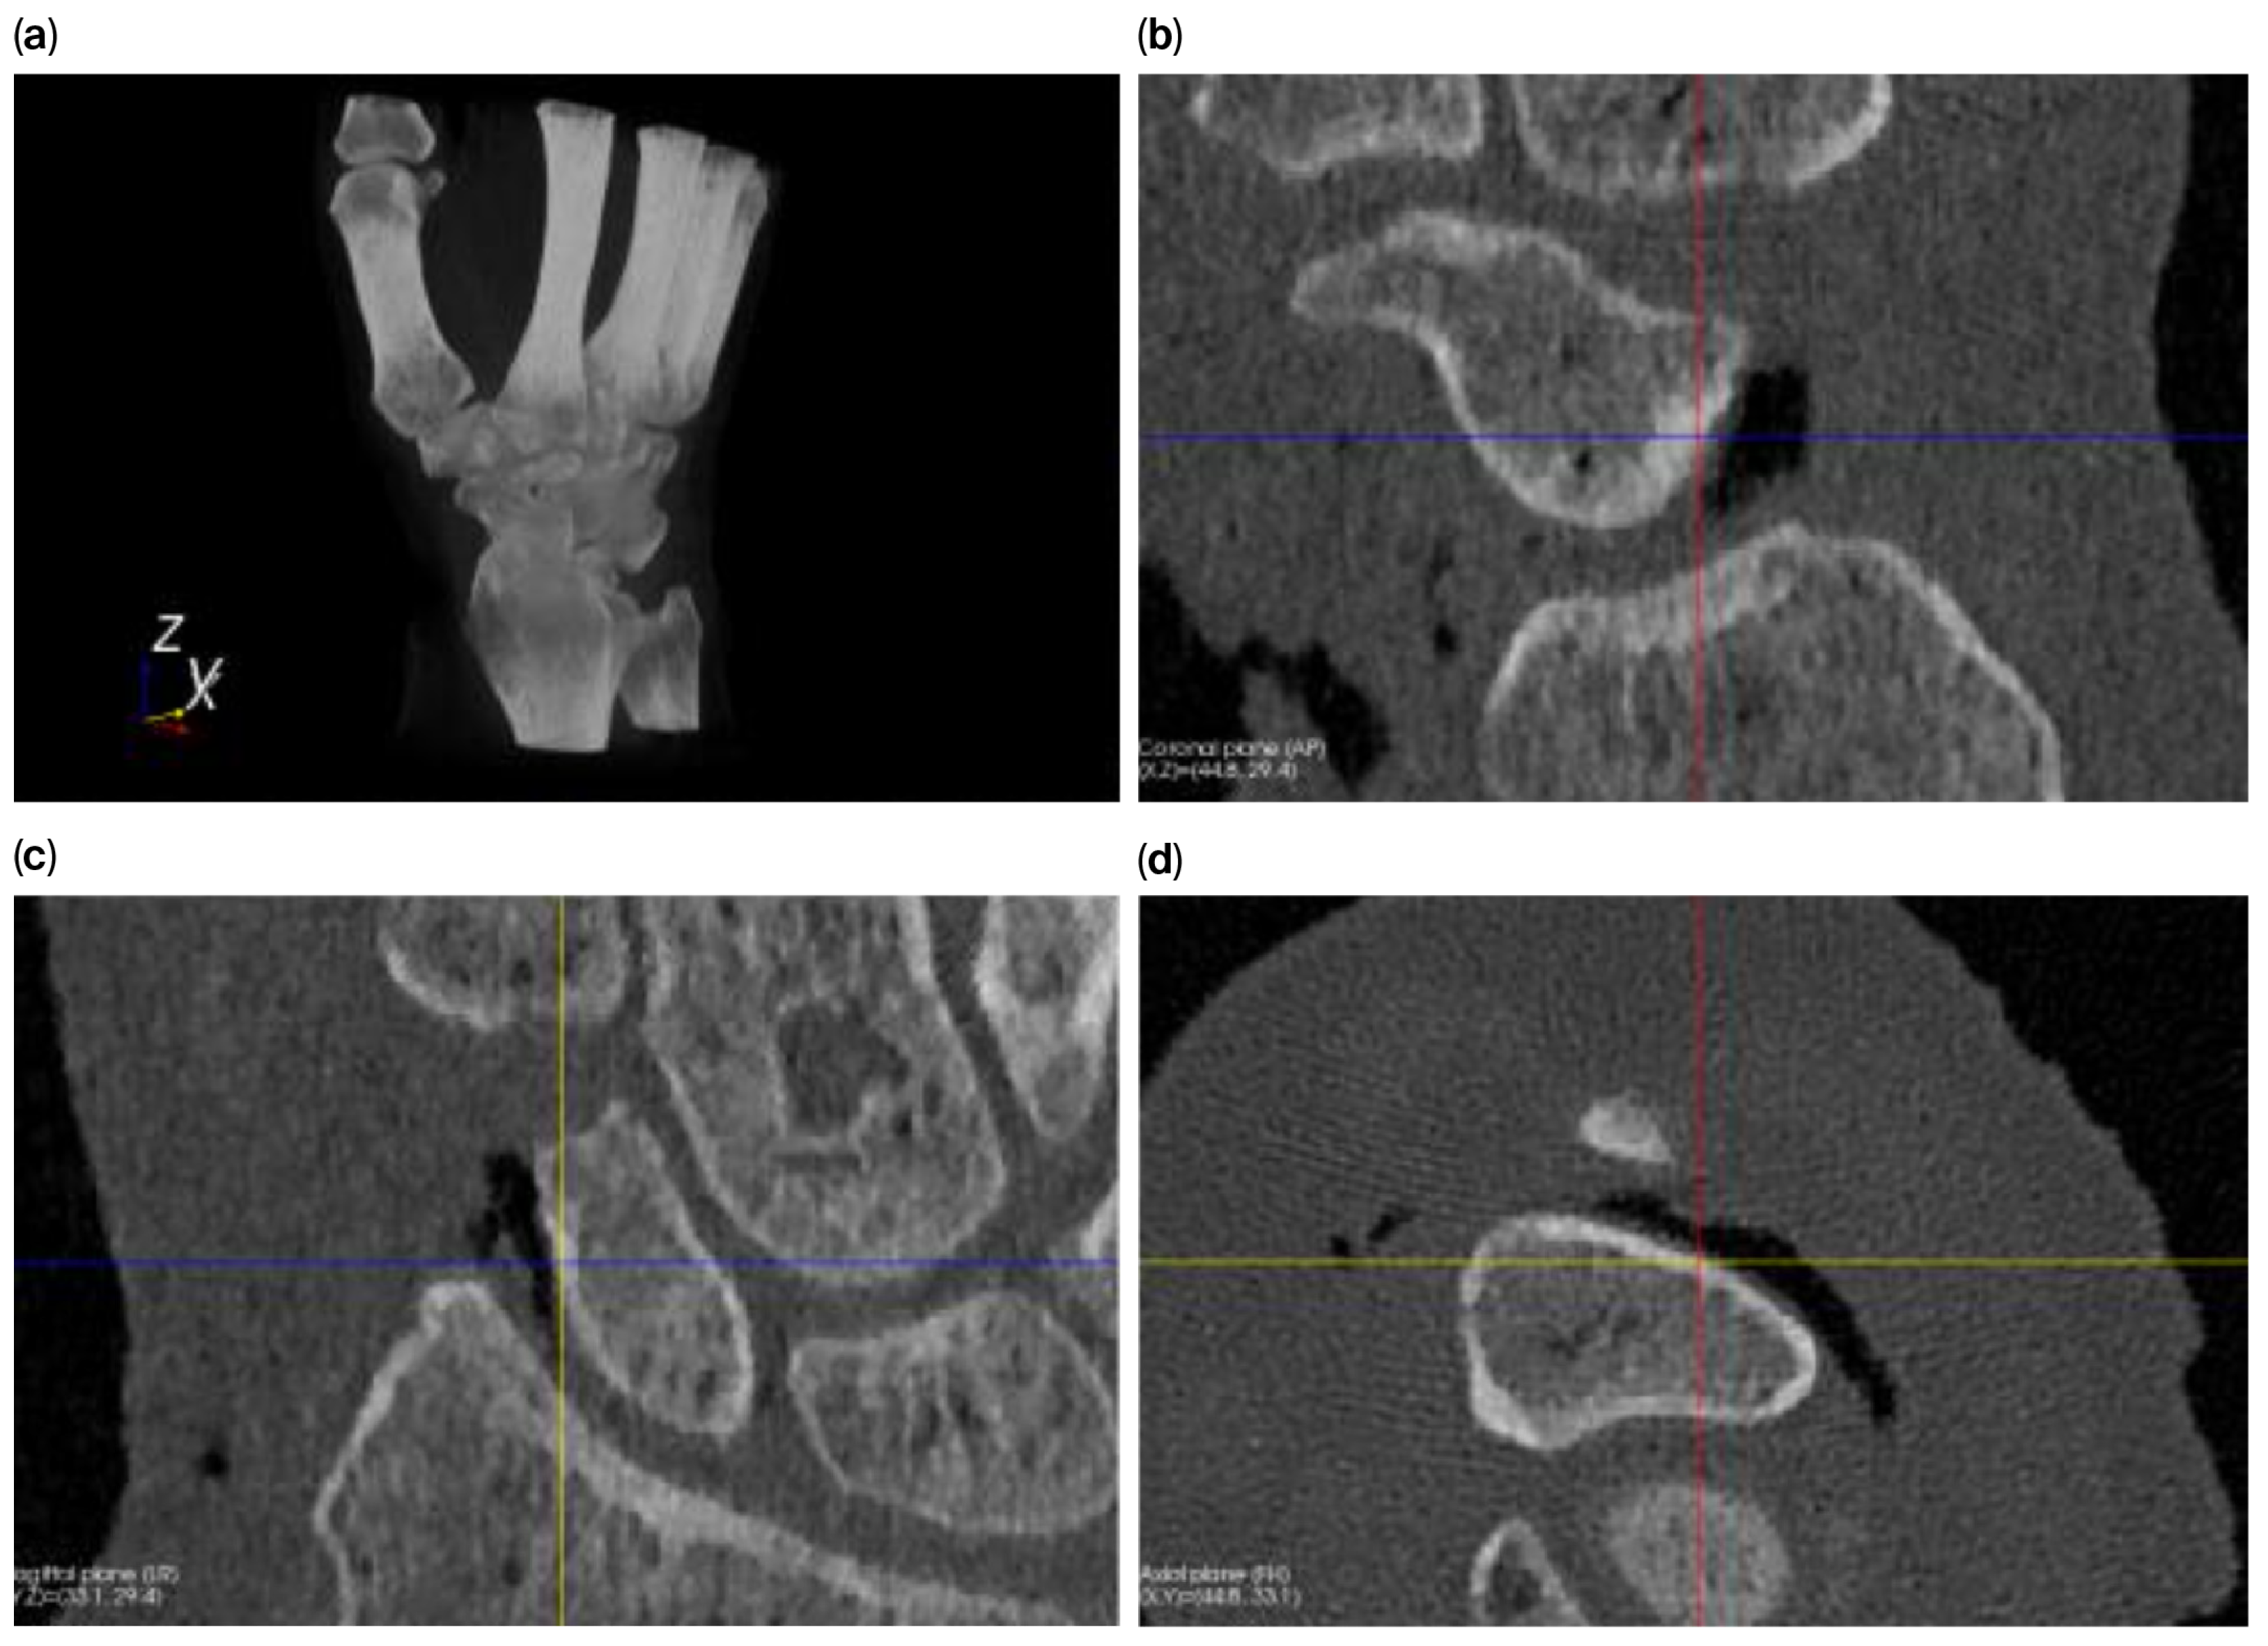

We used a signed-distance heat map to visualize (Figure 3) and quantify (Table 2) the absolute and signed distances between tight and smoothened scaphoid segmentations.

Figure 3. Four standard views of a signed-distance heat map representing the distance between tight/rough and smooth scaphoid segmentations. When the rough scaphoid is larger (blue surfaces), the values are positive; otherwise, they are negative (orange surfaces).

The tight segmented scaphoid shows a slightly rough appearance (Figure 4a), while the smooth alternative (Figure 4b,c) exhibits minor local surface variations up to 0.64 mm, as indicated by the registration of the models. This variation is quantified by the heat map in Figure 4d, but the value is relatively small when compared to the distance between the scaphoid and capitate, as illustrated in Figure 5, which exceeds 0.81 mm.

The joint space thicknesses (JSTs) between the modeled scaphoid and the adjacent bones are of major interest in estimating potential overstuffing. The lowest JST (0.81 mm) was calculated for the scapho-capitate joint. All other JST values were 2 mm or larger, as shown in Figure 5.

The smoothing method adopted in our workflow introduced surface deviations of up to 0.64 mm when compared to the native segmentation. Importantly, these deviations remained below the minimum joint space thickness (JST) observed at the scapho-capitate interface (≥0.81 mm) and the cartilage layers of the distal radius, with values of 0.70 mm (±0.18) at the scaphoid fossa and 0.89 mm (±0.23) at the interfossal ridge [18]. These findings confirm that the smoothing process does not critically affect prosthesis fit within the anatomical joint space.